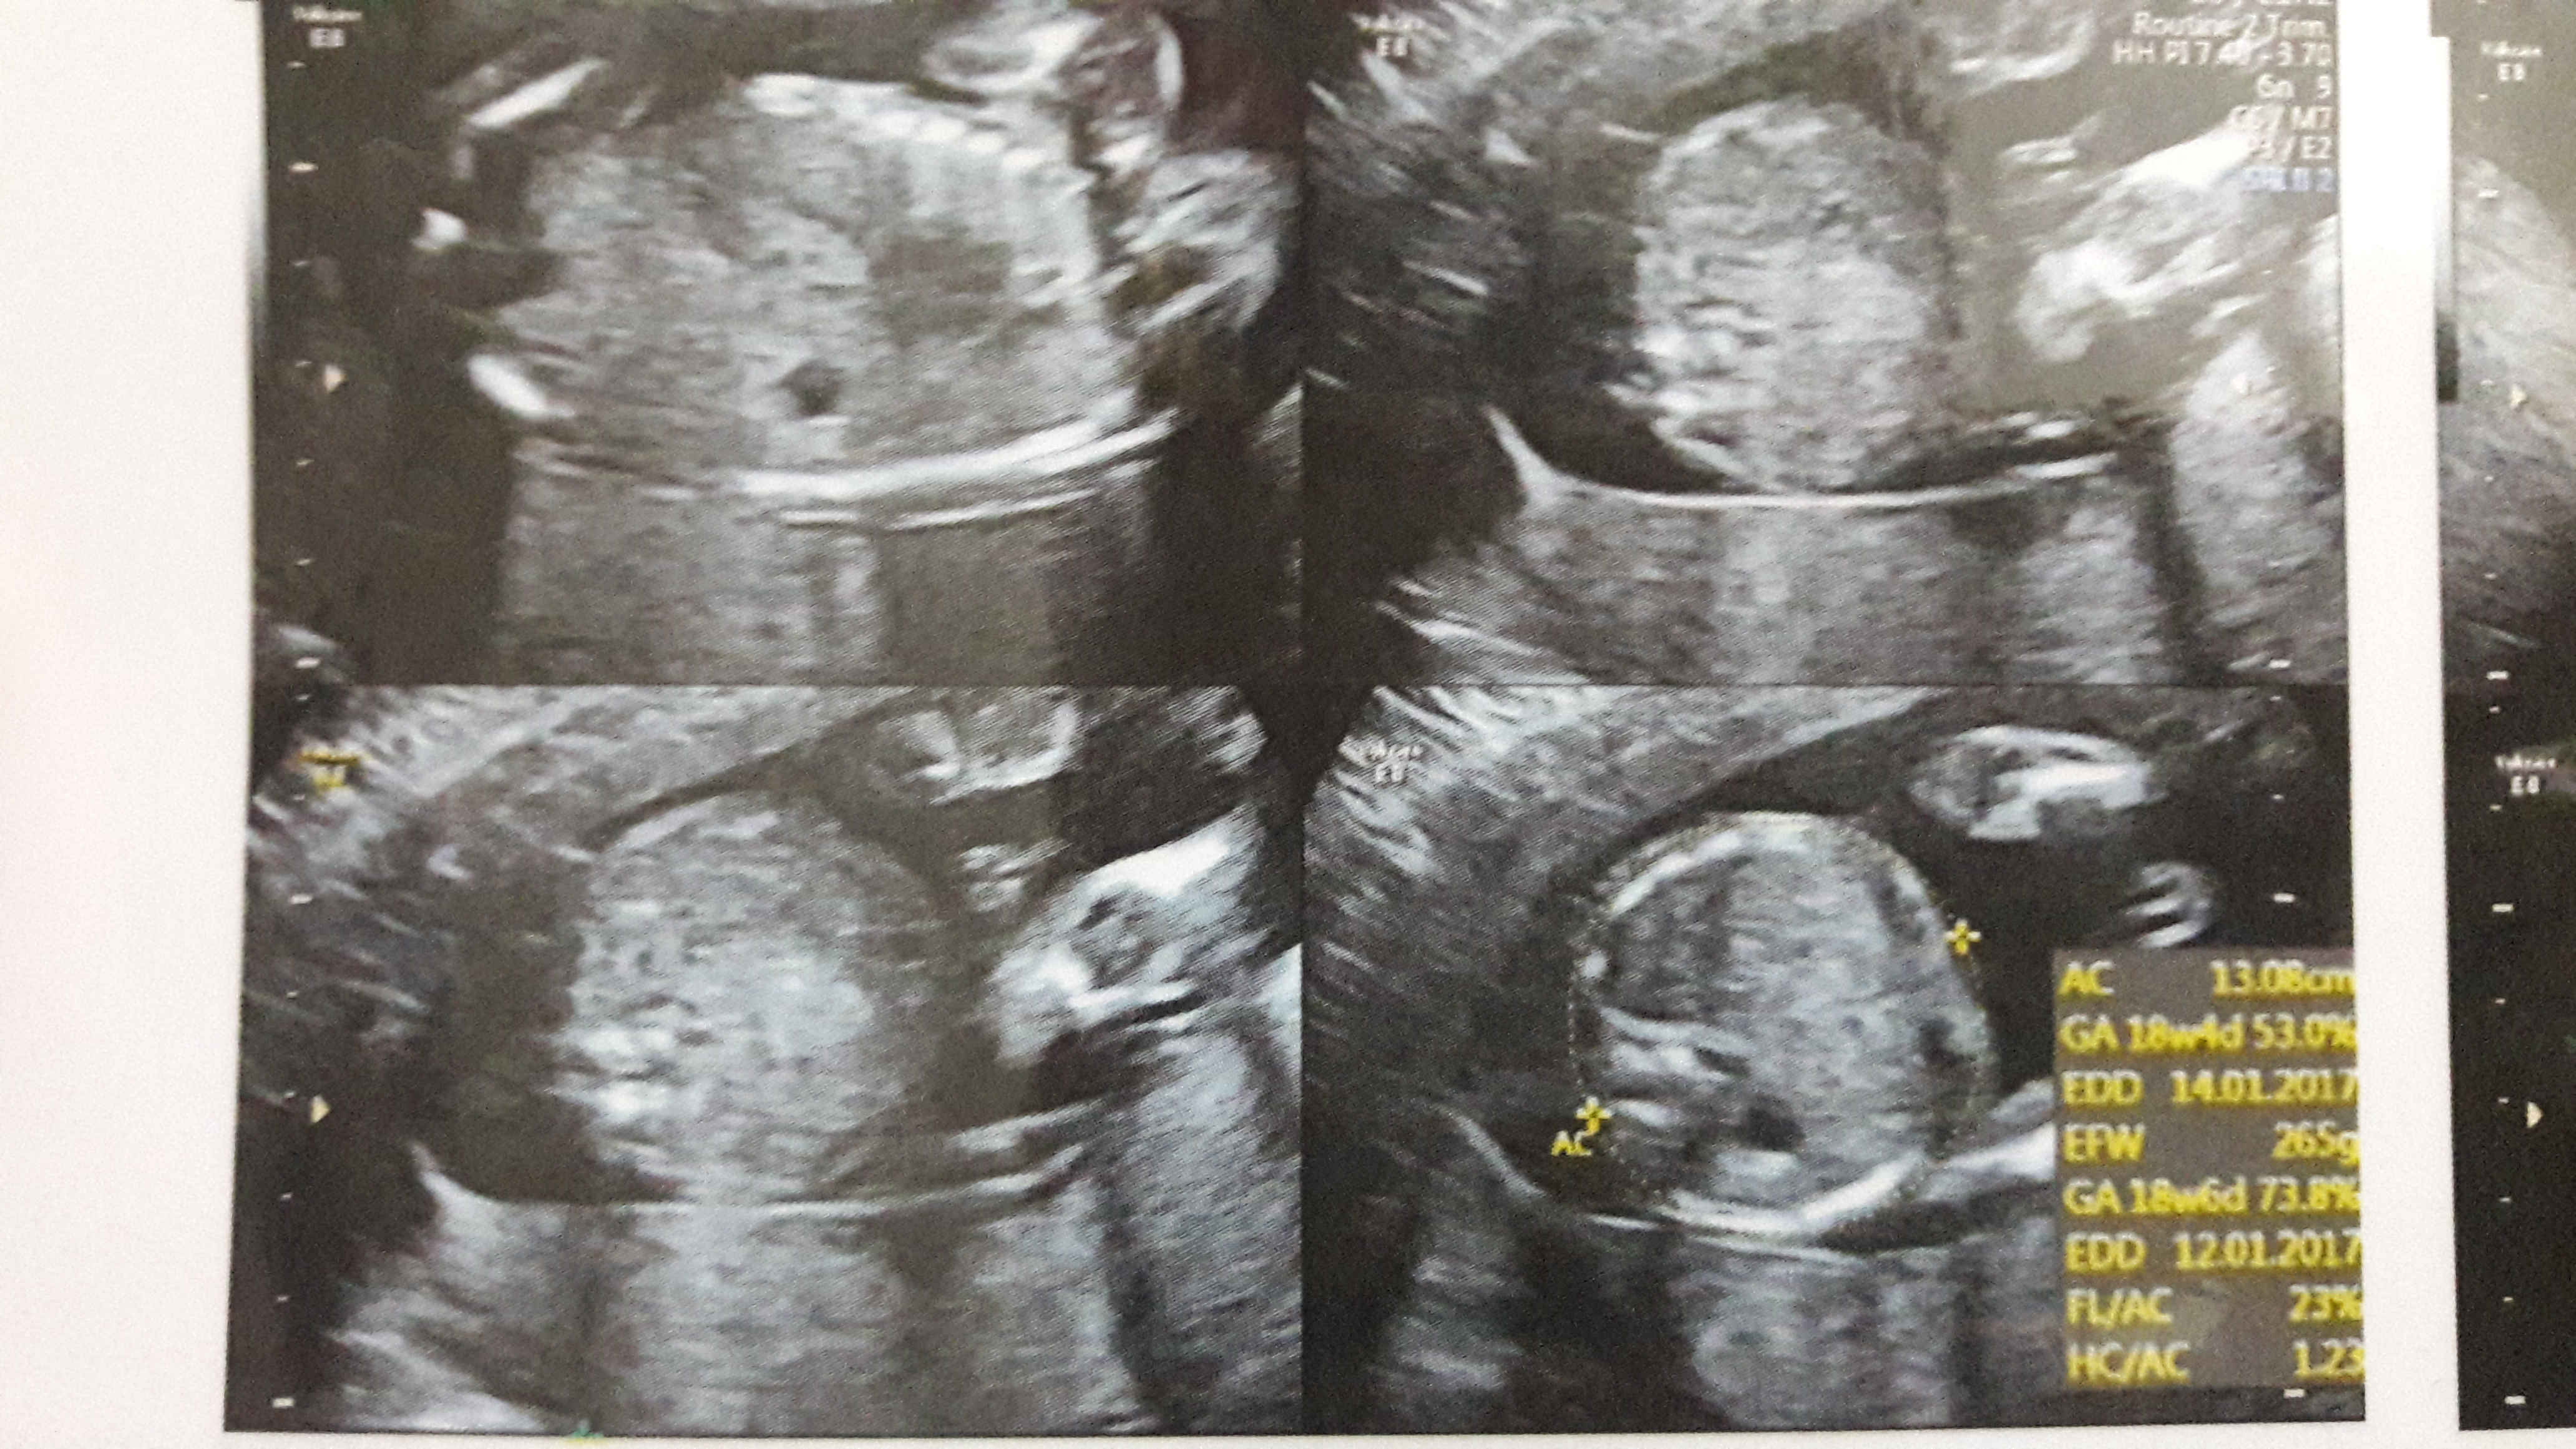

this is my 12 weeks scan, first baby =-) we got told that the sex of the baby could be seen if we wanted to know, we said no as we was wanting a suprise but now I just cant wait to know.!!

I herd about the nub & was wondering what you all thought??